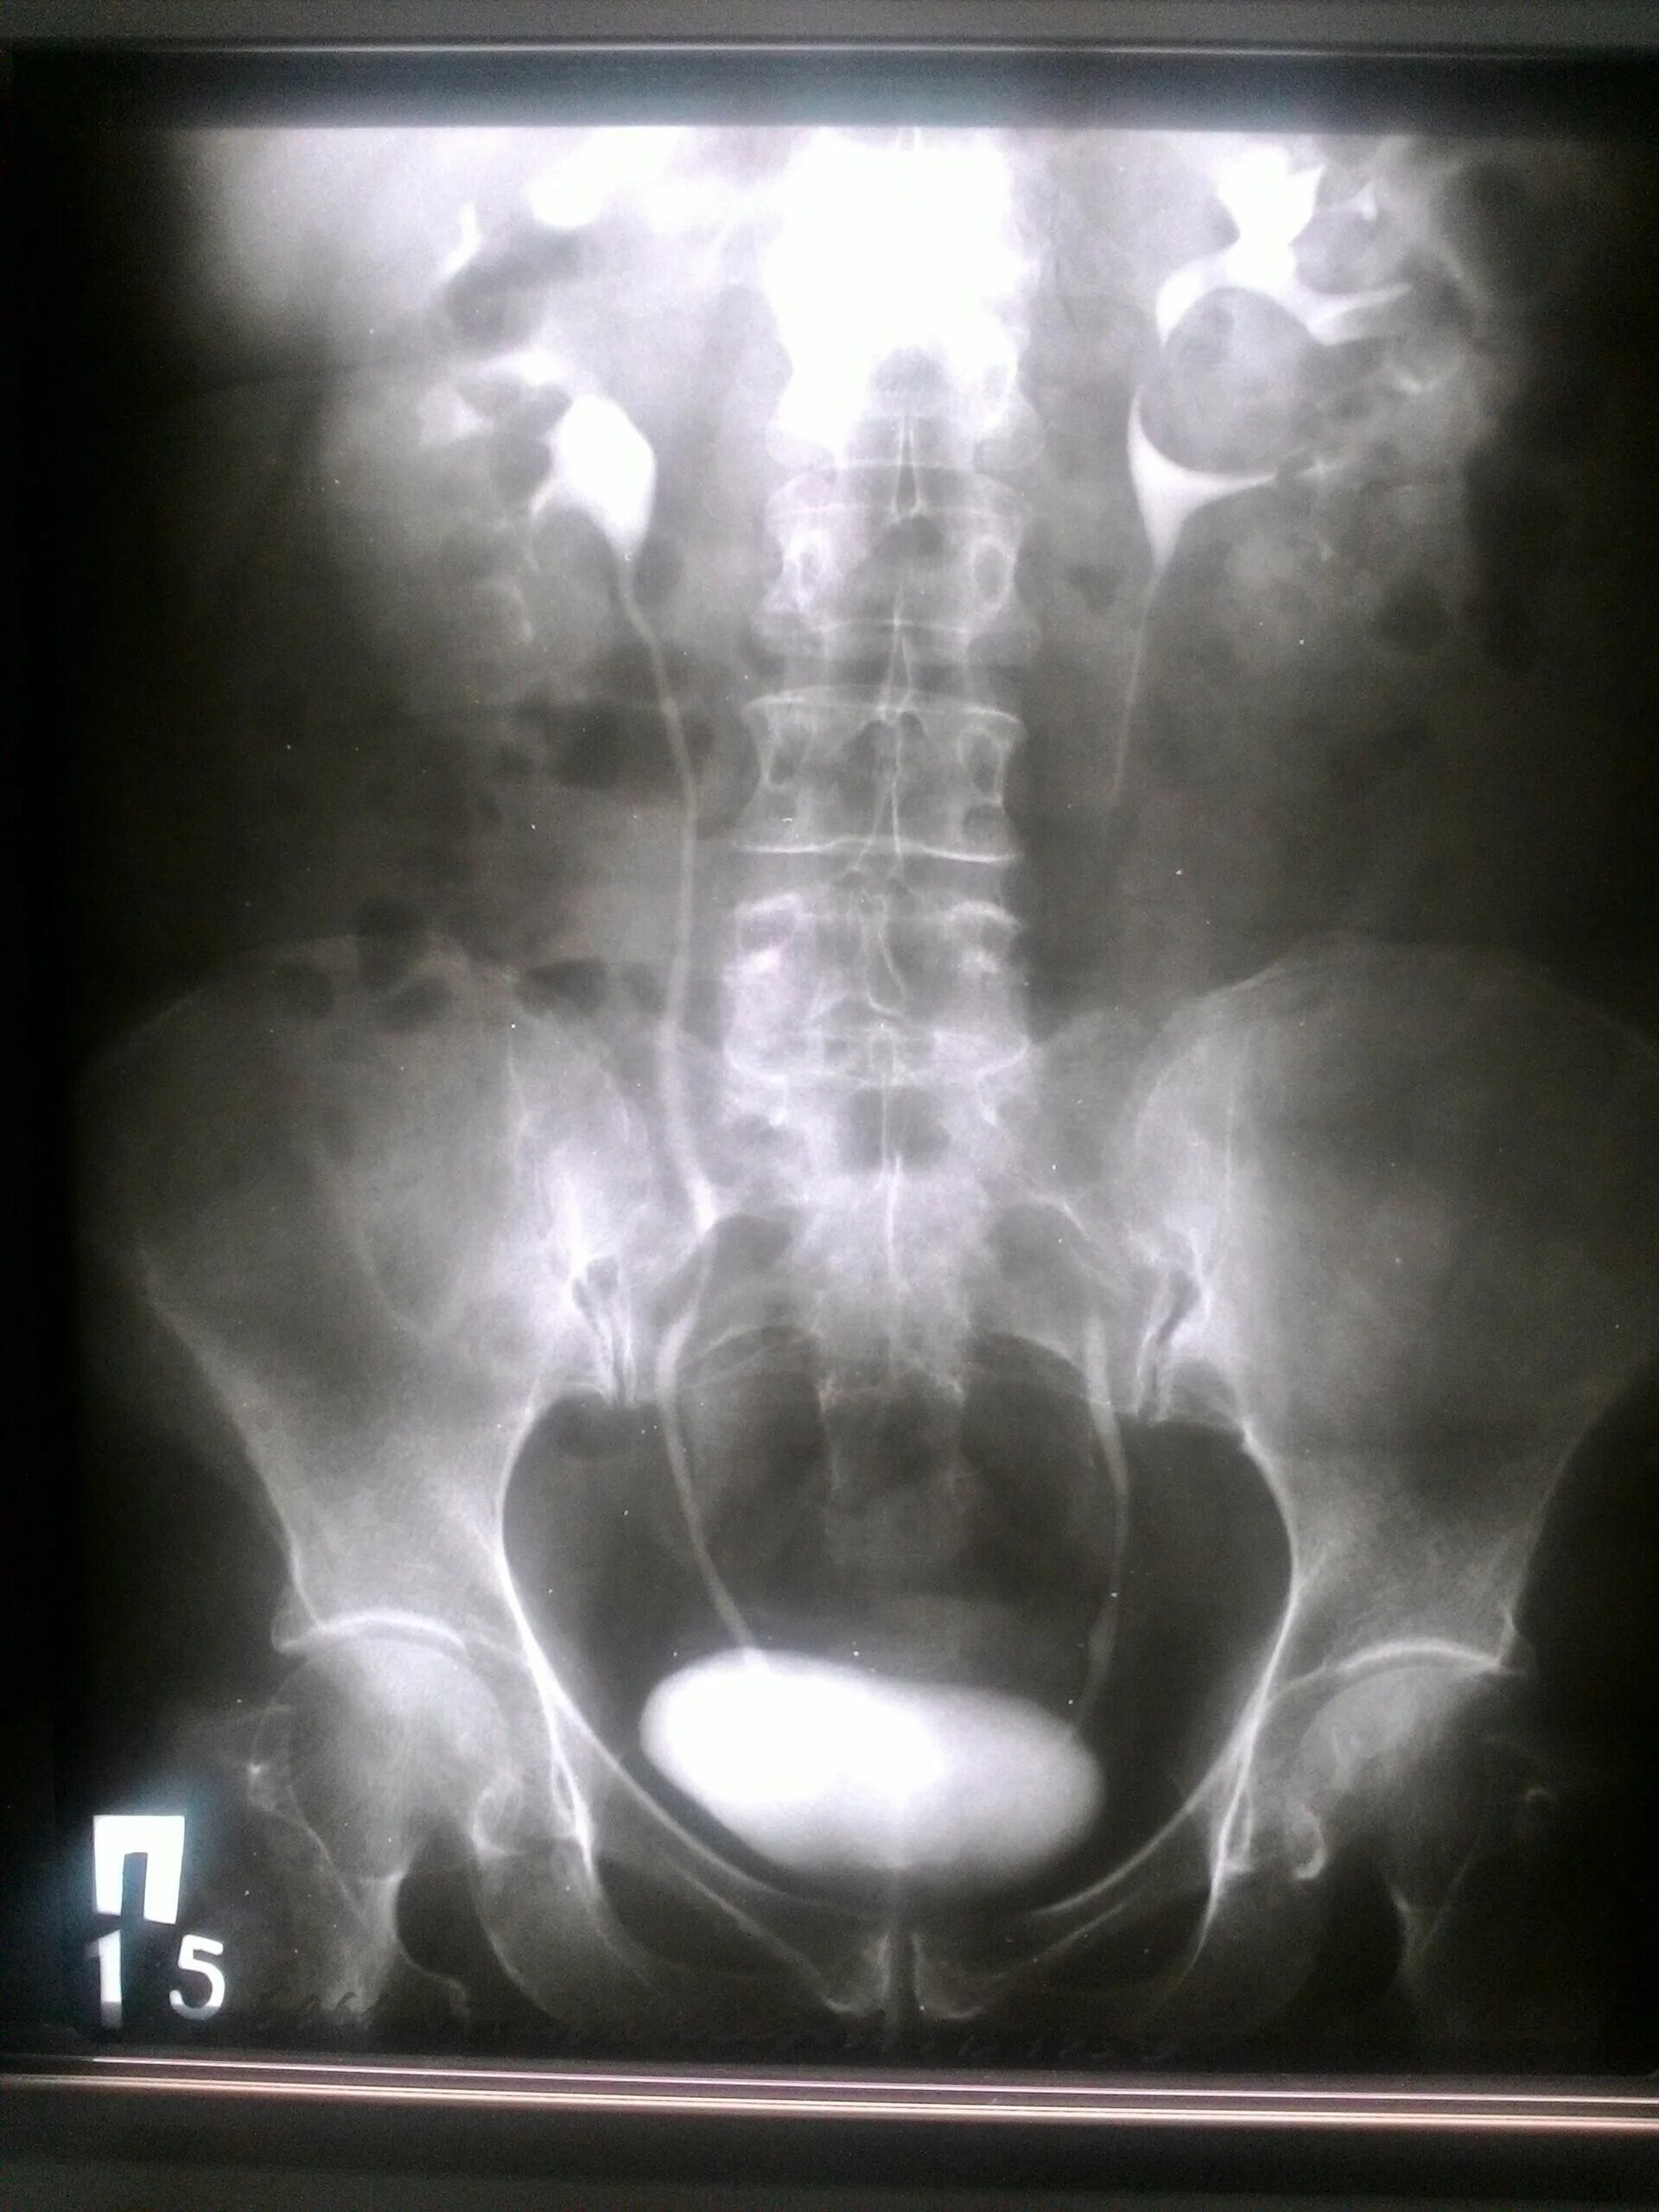

Урография с контрастом